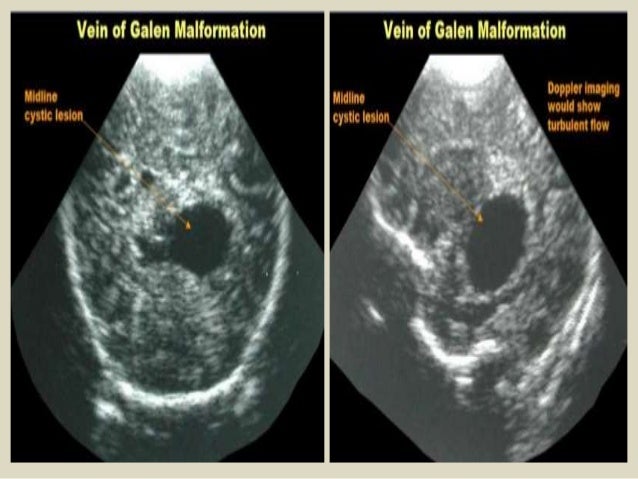

27. 27. Aneurysm of vein of Galen.

28. 28. Gray-scale and Doppler coronal USG demonstrating a cystic midline structure in the region of posterior third ventricle with mass effect. (A) Typical swirl effect is noted on Doppler (B). Findings are highly suggestive of aneurysmal malformation of the vein of Galen. The corresponding axial and sagittal T2W images of MR examination confirming large aneurysmal dilatation of the vein of Galen (C and D)

29. 29. Coronal section - Absent corpus callosum, widely separated frontal horns of lateral ventricles, dilation and posterosuperior displacement of third ventricle. Partial agenesis corpus callosum.